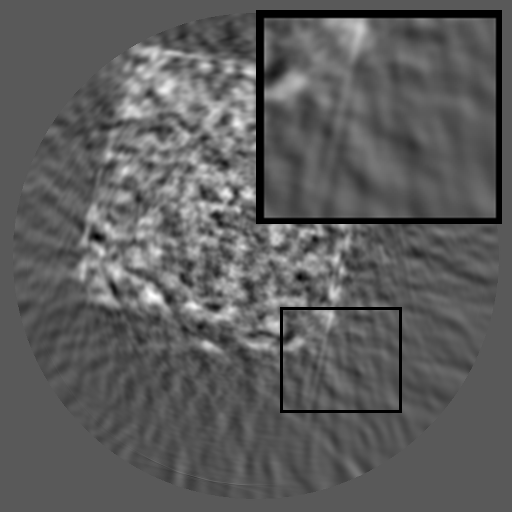

Figure 1: Comparisons of RGB, sinogram and their spectra. Unlike RGB images that have localized frequency components, sinograms exhibit structured spectral distributions due to the Radon transform.

Although inpainting methods have been extensively studied in the context of RGB images (Liu et al., 2024; Zhang et al., 2023; Ko and Kim, 2023; Deng et al., 2022; Lugmayr et al., 2022; Li et al., 2022; Suvorov et al., 2022), their applicability to X-ray sinograms remains relatively underexplored. Most RGB-based approaches rely on the assumption that missing regions can be locally inferred from surrounding pixels. However, this assumption does not readily hold for sinograms, where each pixel encodes an integrated projection value along an X-ray path, leading to globally coupled and highly entangled structures. Several studies have explored sinogram completion using U-Net-based (Zhao et al., 2018; Yao et al., 2024), GAN-based (Valat et al., 2023b; Xie et al., 2022) or Transformer-based (Jiaze et al., 2025) models, and some have incorporated periodicity or reconstruction-based constraints (Li et al., 2019c; Wagner et al., 2023). However, these methods remain largely spatial, focusing on pixel-wise interpolation or appearance realism, and fail to explicitly model the structured frequency domain or the governing physics of sinogram formation, which are fundamentally distinct from those of RGB images. As defined by the Radon transform (Radon, 1917), the detector and angle axes of a sinogram represent distinct physical dimensions, leading to highly directional and asymmetric spectral patterns (see Figure 1). These observations highlight the need to explicitly account for the frequency structure and physical consistency inherent to sinograms when performing data completion.